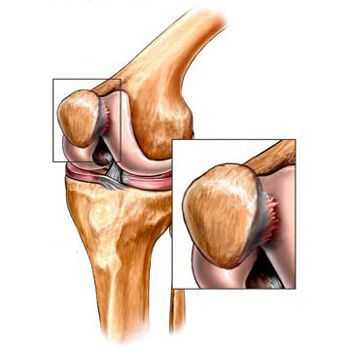

Помимо внутреннего или наружного отдела колена артроз может поражать и поверхности между надколенником и межмыщелковой бороздой бедренной кости. Такой вариант называется пателло-феморальный артроз. [16]

Его причиной, как правило, становится подвывих, перелом или латерализация надколенника.